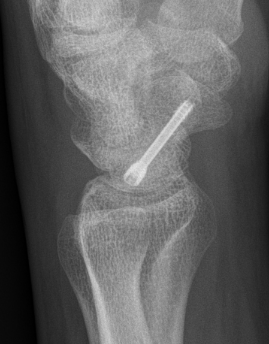

Scaphoid waist fracture 1 mm displaced

Scaphoid fracture with significant displacement

Scaphoid proximal pole fracture